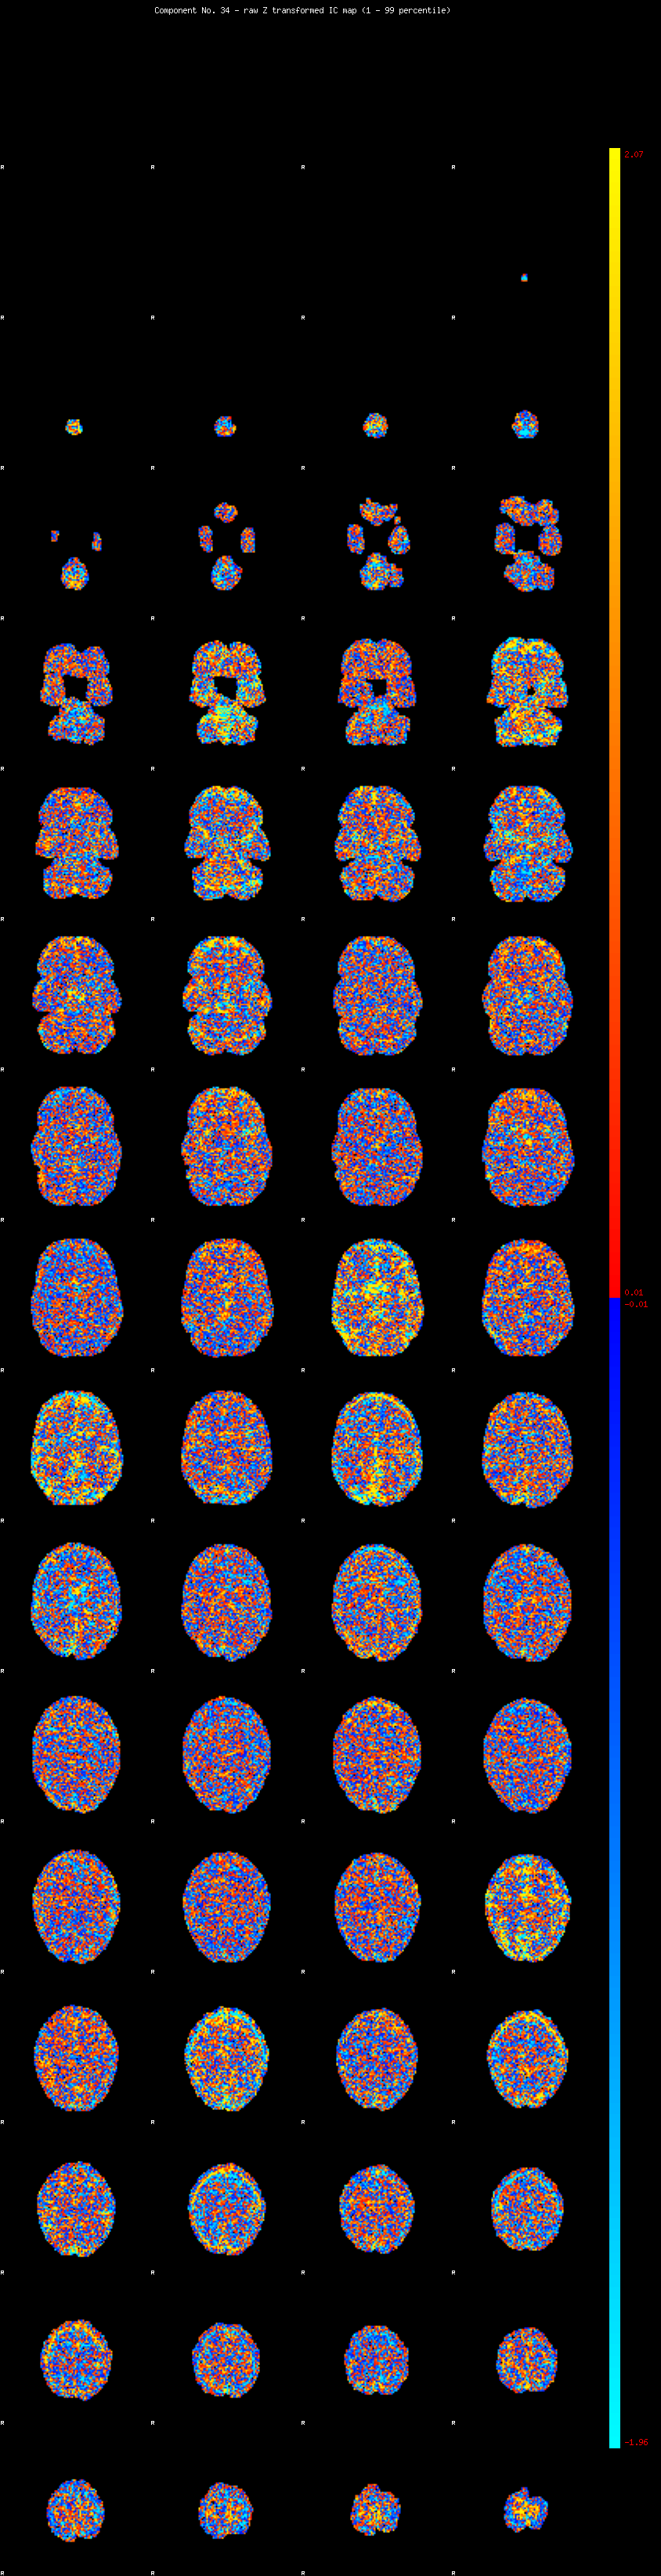

IC_34 Mixture Model fit

Means : 0.000000 2.491848 -2.335351

Vars : 1.000000 2.012908 1.566577

Prop. : 0.927005 0.041760 0.031235